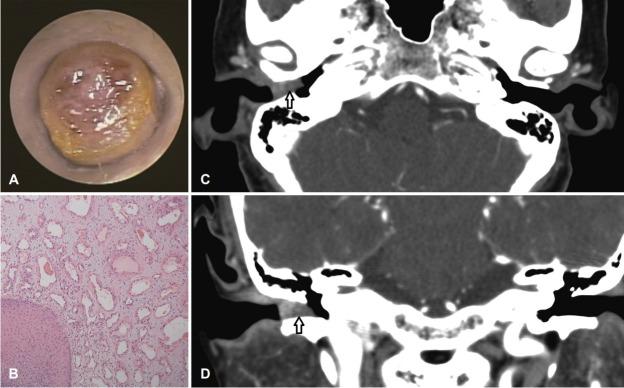

Primary tumors arising from the external auditory canal (EAC) are rare. We describe two cases of mass lesions within the EAC causing slowly progressive hearing loss without otorrhea or otalgia. Otoendoscopic examination demonstrated total obstruction of the EAC, and pure tone audiometry revealed conductive hearing loss. Based on the findings of the histopathologic examination, one patient was diagnosed with venous hemangioma that was treated using surgical resection, and the other patient was diagnosed with diffuse large B-cell lymphoma (DLBCL) that was treated using external-beam radiation therapy. Although primary tumors in the EAC are rare, both benign tumors such as venous hemangiomas and malignant lesions such as DLBCL should be considered as possible differential diagnoses of mass lesions in the EAC.

起源于外耳道(EAC)的原发性肿瘤较为罕见。我们描述了两例EAC内的肿块病变,导致听力缓慢进行性下降,无耳漏或耳痛。耳内镜检查显示EAC完全阻塞,纯音听力测试显示传导性听力损失。根据组织病理学检查结果,一名患者被诊断为静脉血管瘤,采用手术切除治疗,另一名患者被诊断为弥漫性大B细胞淋巴瘤(DLBCL),采用外照射放疗。尽管EAC原发性肿瘤罕见,但静脉血管瘤等良性肿瘤和DLBCL等恶性病变都应被视为EAC肿块病变可能的鉴别诊断。